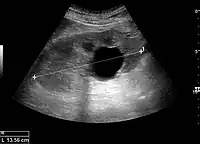

Simple renal cyst.jpg

Simple renal cyst